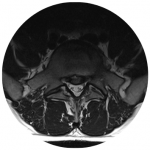

Lendenwirbelsäule

Mikrochirurgische oder offene Dekompression von Bandscheibenvorfällen und Spinalkanalstenosen